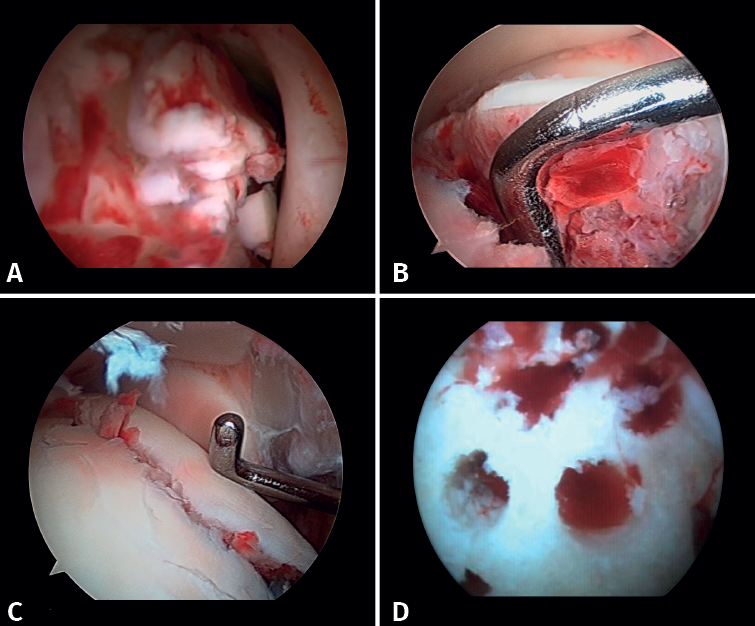

- Diagnóstico de inestabilidad sindesmal: la artroscopia permite la evaluación de la integridad de la sindesmosis y del ECM sobre la radiografía y la TC, sobre todo en la clasificación de las fracturas SER II y IV. Se ha demostrado que la evaluación radiográfica no siempre predice la lesión sindesmal. Además, la artroscopia permite asegurar una reducción anatómica de esta. Takao encontró que el 87% (33/38) de los tobillos con fractura tenían lesiones de la sindesmosis detectadas por artroscopia(20).

La artroscopia permite la visión directa de la sindesmosis y, además, permite su evaluación dinámica(22,21).

- Nos permite diferenciar entre fracturas SER II (en las que no debería existir lesión sindesmal) y fracturas SER IV, en las que sí hay afectación de la sindesmosis, pudiendo estabilizarla(5,23).

- Puede evitar la falsa impresión de un espacio articular medial ensanchado en la fluoroscopia debido a anomalías congénitas.

- Poder visualizar la incisura maleolar junto con el control radioscópico nos permite asegurar un correcto posicionamiento del peroné en la incisura fibularis, sobre todo en las lesiones inestables en las que existe riesgo de mala reducción por acortamiento o rotación del peronéa(5,24).

- Evitar la hipercorrección de la sindesmosis, que es muy artrogénica(5,24) (Figura 6).

Figura 6. A: lesión de sindesmosis; B: control de la reducción para evitar la sobrecorrección; C: control intraoperatorio de la correcta reducción del peroné en la incisura.